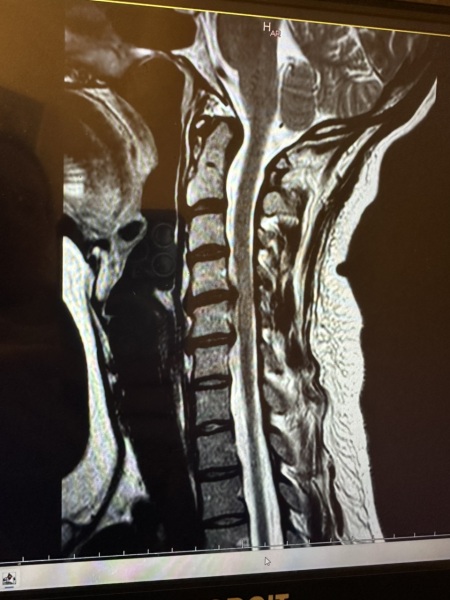

Cervical spinal stenosis

I've been diagnosed with cervical spinal stenosis after having right arm and hand weakness. I'm 35 with two kids.